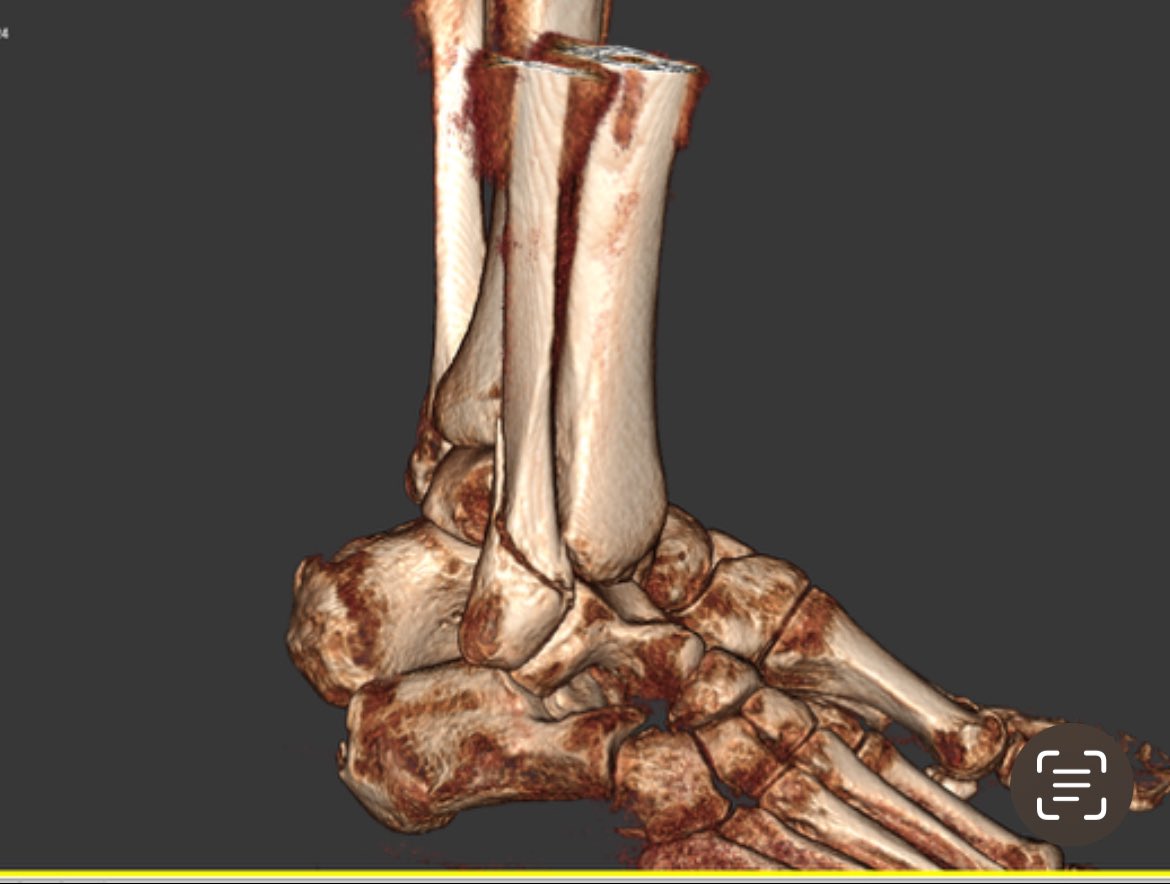

lght.ly/f218o20 Dr Moez Zeiton, DNF Faculty and orthopaedic and trauma surgeon, talks on a podcast with the British Hip Society, and references his work with our Foundation. We are lucky to have you, Moez! #traumasurgeon #surgicaltraining #warsurgery